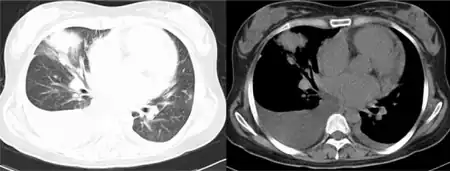

- Radiologic studies show multiple pulmonary infiltrates

Pulmonary infiltration and pleural effusion are usually detected via x-ray.[25]